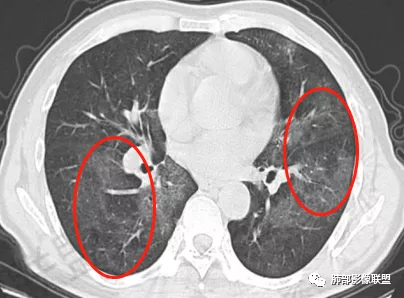

一切∮随缘:双肺多发斑片状渗出影,边界模糊,部分周围可见正常肺组织,其内可见血管走行自然,支气管无明显改变,病变整体以中内带为主,胸膜下受累不明显。

两肺叶弥散性GGo,胸膜下清,职业农民,考虑过敏性肺泡炎,与PCP鉴别。

中年男性,呼吸困难为主。两肺弥漫性GGO,上肺内夹杂小囊。胸膜下累及少,未见明显小叶间隔增厚,两下肺可见小叶内间隔增呈小网格征,左下肺可见索条灶,急性感染临床不符合,第一想到了PCP,中期,所以需要查 HIV。第二肺水肿,但是两肺门不是对称,小叶间隔增厚几乎看不到,所以不考虑。第三过敏性肺炎,肺泡改变?第四滤泡性细支气管炎。第五弥漫性肺泡损伤,药物性?但没有特殊用药病史所以排除。综上还是考虑PCP可能大些。

中年男性,呼吸困难为主,胸部CT双肺由内向外分布为主的磨玻璃影,考虑pjp,鉴别HP,肺水肿。

两肺弥漫性磨玻璃,上肺内夹杂小囊,胸膜下未见累及,中年大叔,考虑PCP,查 HIV。

老年人,呼吸困难,双肺可见广泛磨玻璃影,以中内侧带分布为主,考虑PCP,鉴别过敏性肺炎,PAP。

双肺向心性磨玻璃影,似看见小气囊,首先考虑PJP,查HIV抗体,鉴别CHP,看看外周血嗜酸粒细胞是否高。

男性病人呼吸困难4个多月,既往有慢支肺气肿,影像学表现为两肺弥漫性的渗出性的改变,马赛克表现,肺动脉主干明显增粗,肺动脉高压的表现。注意排除心源性的肺水肿,肺泡炎、肺出血;感染性病变:过敏性肺炎?卡肺?

中年男性,呼吸困难为主,两肺弥漫性磨玻璃,夹杂小囊腔,肺门向外外分布,月弓征,建议临床排查pcp,鉴别hp

中年男性,胸闷气急为主,劳力后加重,病史像心源性,但冠脉条件看起来不错,无胸腔,心包积液,支气管管壁也无增厚,小叶间隔也无增厚,肺水肿不太像。pjp,未提供相关病史,起病四月无热咳,不会首先考虑。病灶以磨玻璃渗出为主,有马赛克灌注空气潴留,提示小气道病变,部分层面有树芽样改变,过敏性肺炎首先考虑,建议询问职业、工作环境、服药史。hiv检测排除pjp

大雄:中年男性,呼吸困难4月余,其他无异常。影像学表现双肺弥漫磨玻璃影,中上肺及中内带分布为主,伴下肺少许纤维化。第一印象比较符合PCP,但是病史四个月不伴有发热及干咳,似乎可能性不大。影像学还需要考虑的有HP,PAP,药损,EP。HP和药损需要病史支持,询问有无环境暴露以及药物相关因素。AEP从病史可以排除,CEP没有嗜酸增高,也基本排除。PAP影像学不太典型,但临床符合,可以放鉴别诊断剩下的DAD和DAH基本不用考虑了,病史不支持。再有就是慢性肺水肿,需要有临床的诱因。

1、双肺从中心向外周对称性弥漫分布的磨玻璃密度影,无重力分布特点

2、中内带分布为主,胸膜下较少受累,可见月弓征

3、下肺纤维灶形成

结合患者症状典型的呼吸困难症状及影像学改变,临床症状轻,影像重,双肺从中心向外周对称性弥漫分布的磨玻璃影,无重力分布,胸膜下受累不明显(月弓征),呈典型的间质性改变,需要考虑肺孢子菌肺炎的可能,临床上需要结合有无HIV、使用免疫抑制剂病史、器官移植等免疫缺陷病史,还可以借助化验CD4细胞、LDH等进一步判断病情。